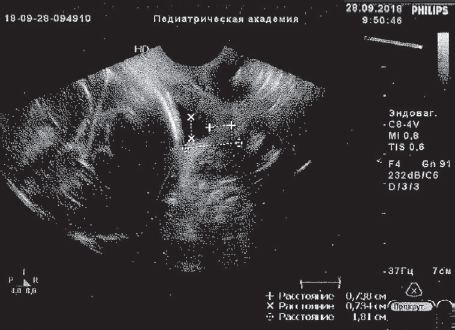

Пациентка М., 35 лет. В анамнезе: хронический тонзиллит, варикозная болезнь нижних конечностей, 1 срочные роды, два года назад — лазерная эксцизия шейки матки по поводу эрозированного эктропиона. Вторая беременность: в сроке 7 недель проводилось стационарное лечение при угрозе прерывания с формированием ретрохориальной гематомы на фоне кольпита. Неоднократно, несмотря на лечение, в динамике из выделений цервикального канала высевалась кишечная палочка. В дальнейшем трижды госпитализировалась по поводу угрозы прерывания (получала магнезию, утрожестан, амоксиклав и др.), В сроке 19 недель выявлена ИЦН, введен АРП. Поступила в ПЦ СПбГПМУ при беременности 25 недель и 3 дня по поводу угрожающих очень ранних преждевременных родов на фоне ИЦН (длина шейки матки по данным УЗИ — 6,9 мм, цервикальный канал на всем протяжении расширен до 11 м). В посеве из влагалища выделена кишечная палочка, в анализе крови данные за умеренную гиперкоагуляцию, СОЭ 44 мм/ч, ЛИИ — 3,2 усл. ед. Получала комплексную медикаментозную терапию (трактоцил, профилактику РДС, клексан и др.), три сеанса малообъемного МПА в сочетании с лазерным (№ 5), ультрафиолетовым (№ 6) облучением крови. Ослож нений не было. При контрольном УЗИ отмечено формирование незначительной сохранной части шейки матки, которая составила 7,3 мм (рис. 4, 5).

Рис. 4. Данные ультразвукового исследования пациентки М. до курса эфферентной терапии

Fig. 4. Ultrasonic examination of patient M. before efferent therapy